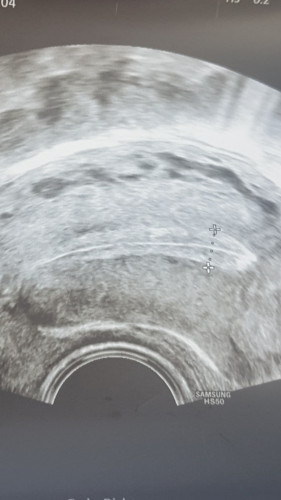

Ich hatte ein künstlichen kryo Transfer im Ausland. Mein FA in DE sagte an ZT9 dass er Progesteron geben würde für 5 Tage und den Transfer ansetzen würde, da Gbsh bei 8mm sei und sehr schön dreischichtig.

Mein FA sagte dann an diesem Termin, es sieht sehr schlecht aus, nicht mehr dreischichtig, 12.9 mm Schleimhaut, warum ich denn nicht vorher transferiert hätte. Jetzt rät er davon ab. Meine Schleimhaut hätte sich schon ins schlechte umgewandelt, es wäre was in Gange.Den Progesteron Wert kannte er aber zu diesem Zeitpunkt noch nicht, da das Bluteergebnis erst nachmittags da ist. Er lag dann bei 0.45 μg/l

Meinem Arzt im Ausland schickte ich die Ultraschallbilder und den Wert und sagte ihm dass es nicht mehr dreischichtig ist und mir abgeraten wurde.